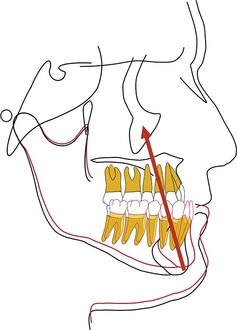

Keles et al.34 studied the effects of varying the force direction on maxillary orthopedic protraction in two groups of patients. The first group received protraction headgear with a force applied by intraoral elastics and the second group received a force applied with a modified protraction headgear as described above.9 The authors reported that in the first group the maxilla rotated counterclockwise (Fig. 16-10), resulting in downward and backward rotation of the mandible, while in the second group an anterior translation of the maxilla with no to minimal mandibular rotation occurred. This important study showed that predictable changes can be achieved in the direction of maxillary advancement with desired or without undesirable mandibular changes.

Figure 16-10 Force diagram of a protraction headgear device using intraoral elastics to deliver force. Note the clockwise moment on the midface and dentition resulting in a downward and backward rotation of the mandible.

By changing the point of force attachment on the facemask or outer bow of the headgear, the vertical dimension of the face can be very nicely controlled. This is especially important in Class III patients with a long vertical dimension and a steep mandibular plane. Similarly, in Class III patients with a flat mandibular plane and a deep bite, a force below the level of the occlusal plane may be more desirable to rotate the mandible downward and backward (see Fig. 16-10). A line of force closer to the center of resistance of the midface will deliver a translatory force (Fig. 16-11) and a line of force closer to the occlusal plane has a rotational force (Fig. 16-12).